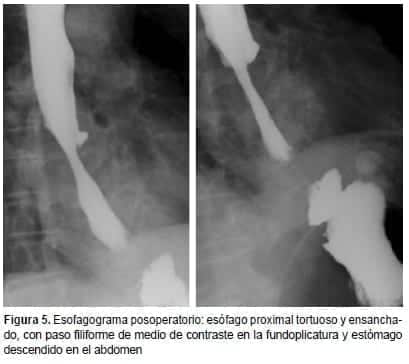

En la radiografía posoperatoria, se observó mejoría de la zona de estenosis y el estómago se encontró dentro del abdomen. En un nuevo esofagograma con bario, se observó paso filiforme del medio de contraste a través de la unión gastroesofágica, lo cual puede considerarse un hallazgo esperable debido a la reducción exitosa del estómago al abdomen, normal en este tipo de procedimientos (figura 5).